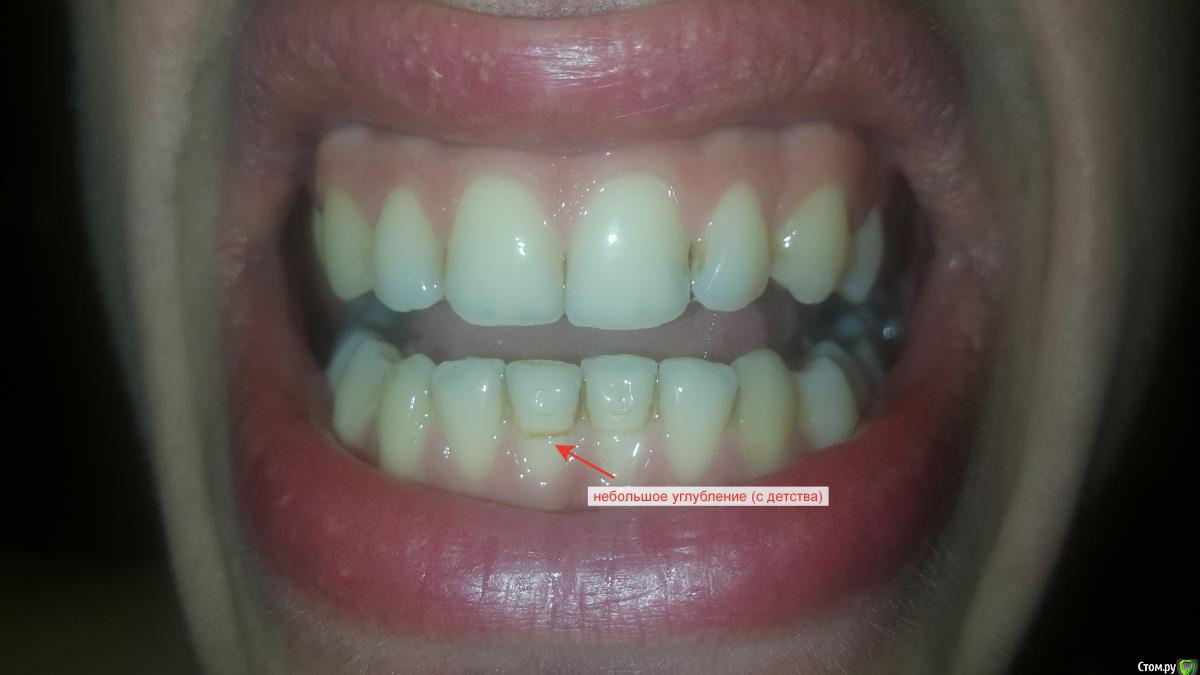

3) На нижнем переднем зубе у меня небольшое углубление с внешней стороны. Уже давно, не знаю откуда. Опять же, никто из врачей не обращает на это внимание. Хотел узнать, стоит ли поставить пломбу в это место для упрочнения зуба?